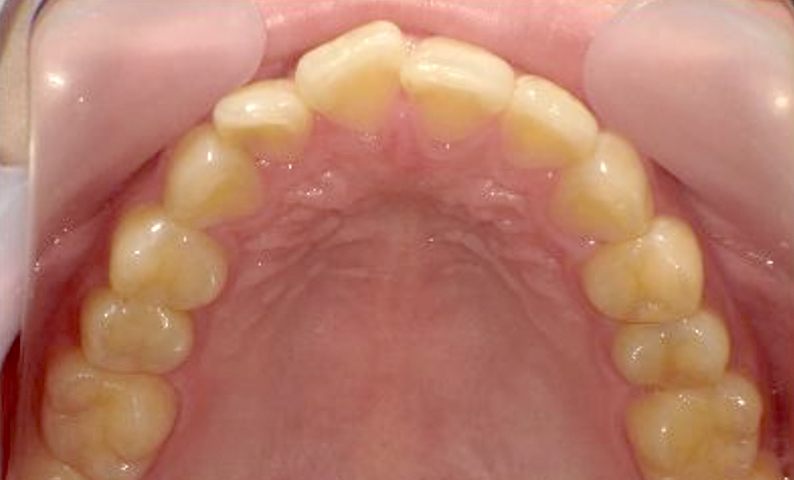

症例_001 前歯「捻転歯」症例

治療期間:6ヶ月金額:48万円+税20代女性少しのねじれ捻転歯下の八重歯

| Before | After |